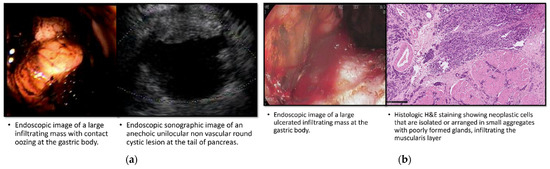

Table 3 provides a comprehensive description of all nine cases of gastric cancer identified in our cohort, including both patients with known IPMNs and those in the control group. In the IPMN group, four cases of gastric cancer were diagnosed during the initial EGDs. These cases presented with various characteristics, such as a large ulcerated infiltrating mass at the gastric body (Figure 1a), an infiltrating mass with contact oozing at the gastric body (Figure 1b), a partially obstructing, circumferential, ulcerated, irregular mass at the gastric antrum (Figure 1c), and a large friable ulcerated mass at the gastric fundus (Figure 1d).

Figure 1.

Endoscopic, sonographic, radiologic, and histologic imaging of IPMN patients diagnosed with gastric cancer in their first EGD. (a) Case 1; (b) Case 2; (c) Case 3; (d) Case 4.